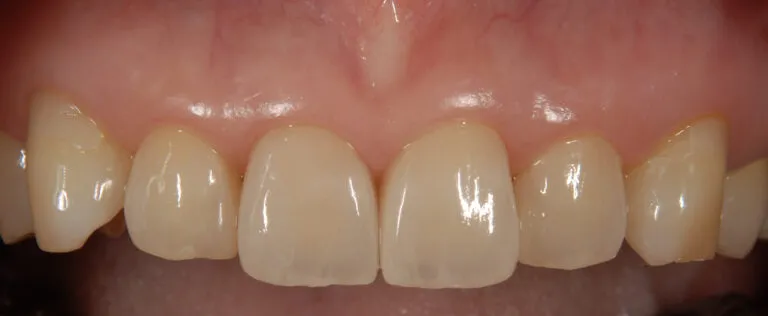

症例5

- 主訴

- 前歯をきれいにしたい

- 治療内容

- 前歯4本をラミネートベニアによる修復

- 治療費

- 35万

- 治療期間

- 2ヶ月

- 通院回数

- 5回

- 想定されたリスク

- 補綴装置の脱離、破切

- コメント

- 最小限の歯の切削量で審美性が改善されました

before

after